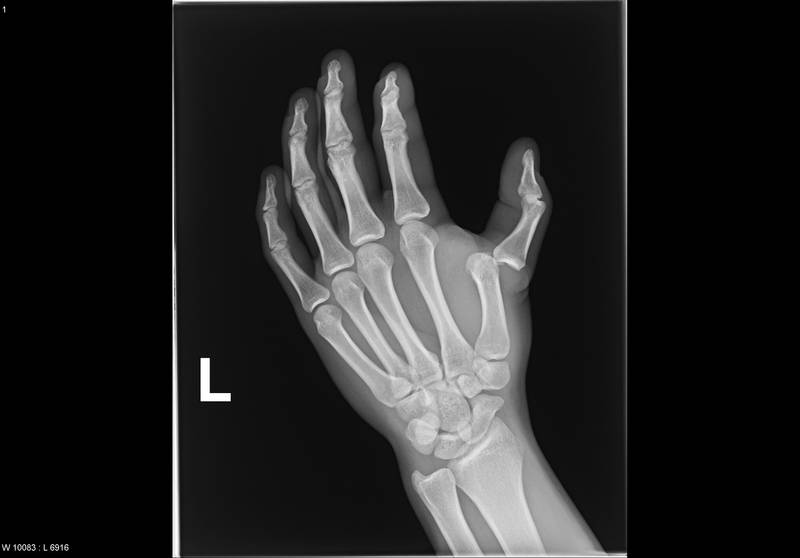

Для установления причины болевого синдрома используются инструментальные диагностические методы — рентгенография, артроскопия, КТ, МРТ. При подозрении на инфекционное происхождение патологии проводятся бактериологические, серологические исследования биологических образцов. Тактику лечения определяют вид обнаруженного заболевания, стадия его течения, степень поражения тканей, количество возникших осложнений.